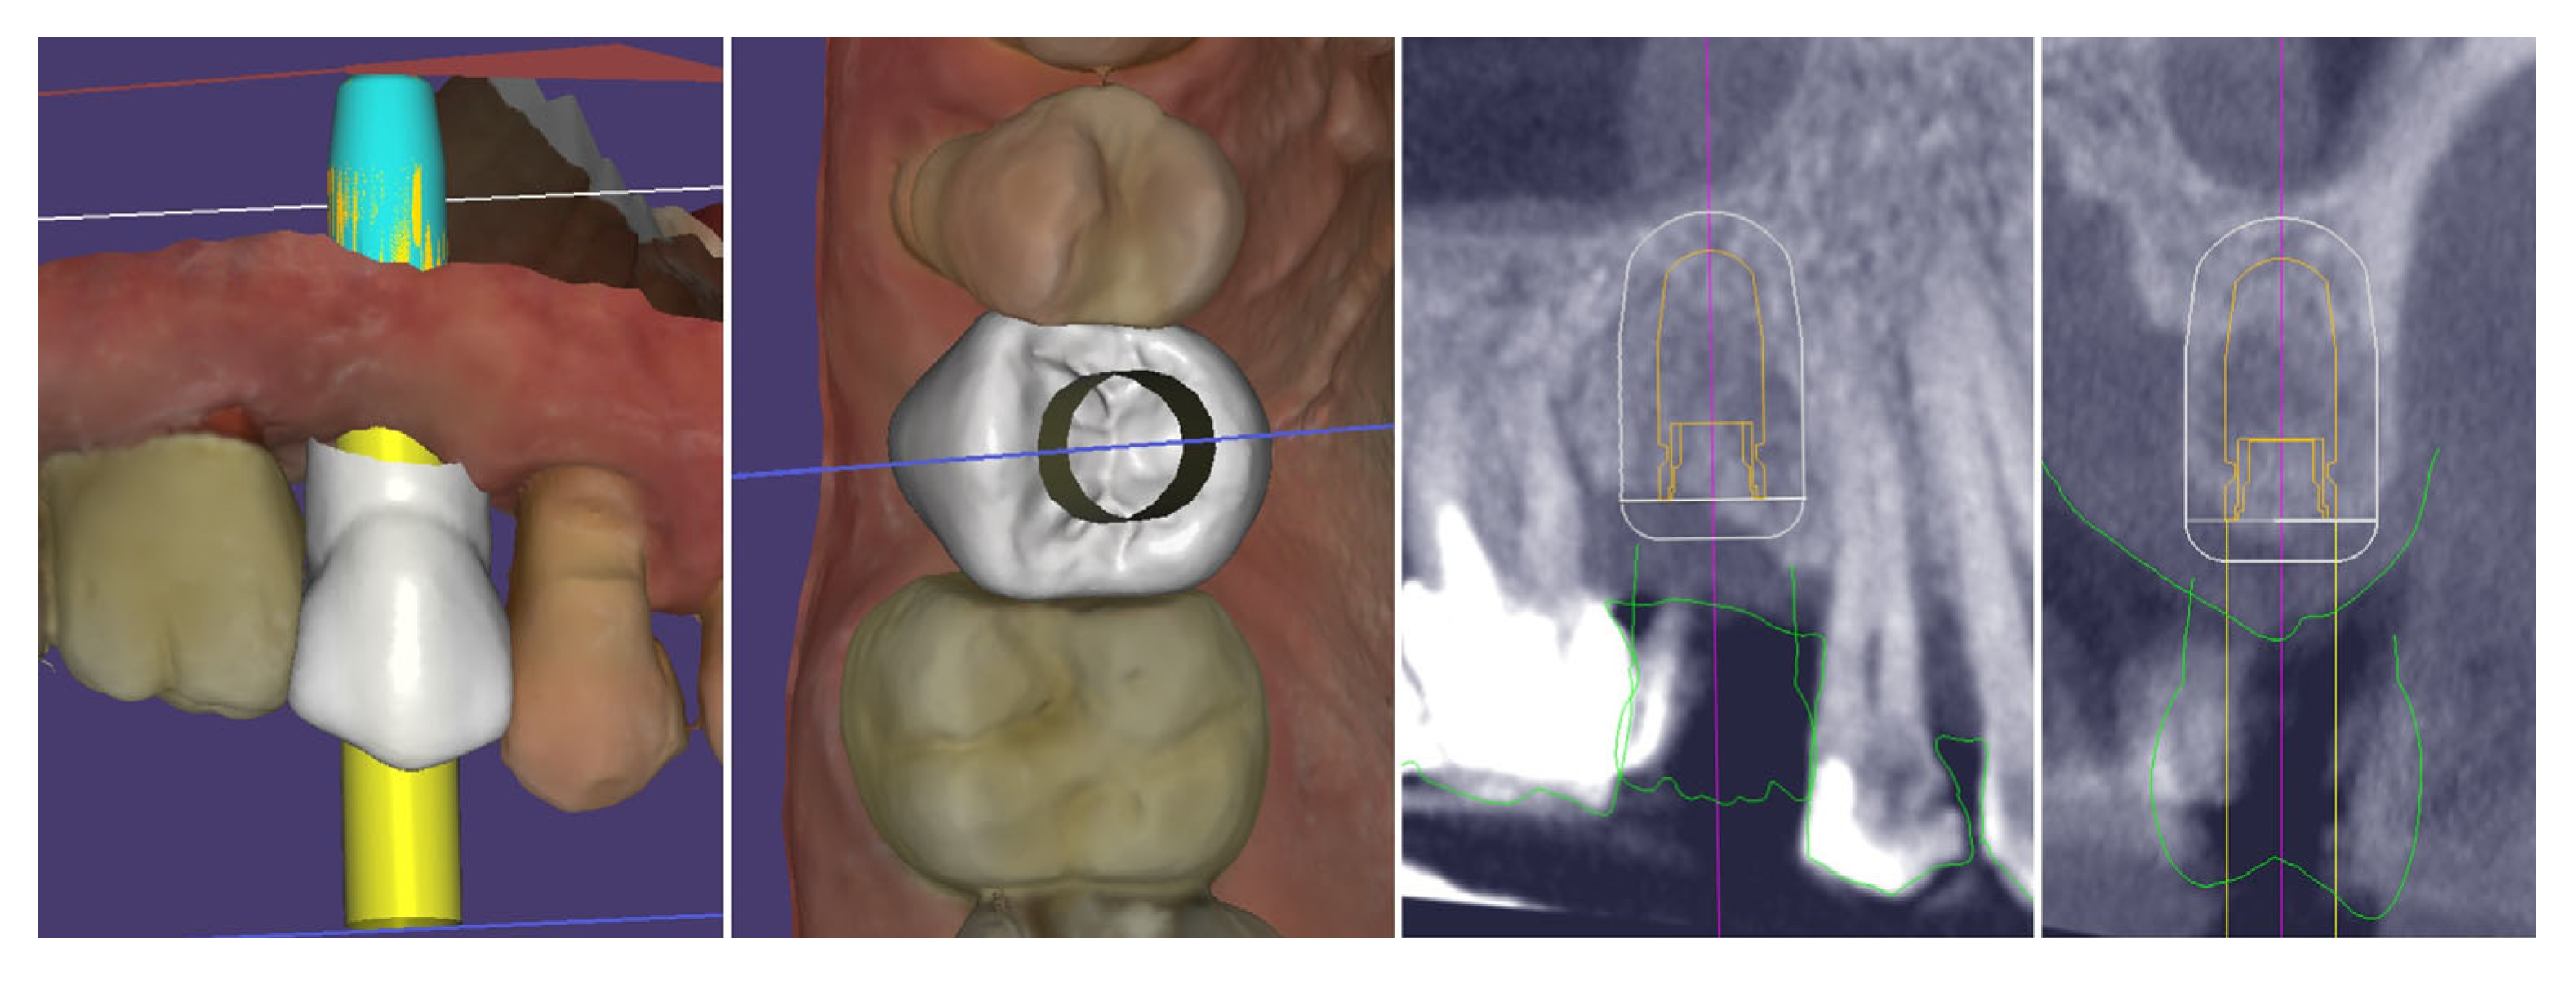

Digital planning of the dental implant was performed. It was determined that there was sufficient crestal bone volume to place the implant in the most appropriate prosthetically oriented position, for which a surgical guide was prepared for fully guided implantation (Figure 5).

Figure 5.

Digital planning of the dental implant.

The performed measurements showed adequate soft tissue dimension (≥3.5 mm) for stable peri-implant tissues crestally, 4.3 mm, and palatally, 5.4 mm, but at the buccal site, a pronounced volume deficiency was detected (2.3 mm soft tissue thickness), for which a soft tissue augmentation procedure was planned (Figure 6).

Figure 6.

Soft tissue dimensions analysis.